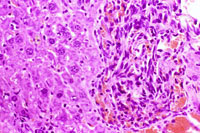

A hemangioma has destroyed the normal hepatic parenchyma. A thrombus is present at the top of the hemangioma; high magnification shows dilated vascular channels lined by flattened endothelial cells. There is minimal atrophy of hepatic cords.